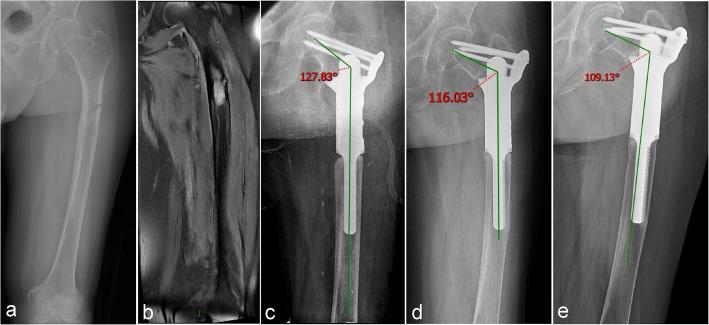

A retrospective analysis of 25 patients treated at two centers with wide resection for primary or metastatic bone tumors (femur, tibia, humerus) followed by reconstruction using ultra-short stem intercalary prostheses combined extracortical plates. Clinical outcomes were assessed using the Visual Analogue Scale (VAS) and Musculoskeletal Tumor Society (MSTS) score. Survival rates were calculated using the Kaplan-Meier method, and complications were classified according to the Henderson system.

The mean follow-up was 20.2 months (range, 3-101 months). The average length of the ultra-short stems was 41.3 ± 9.6 mm. Mean operative time was 164 ± 61.3 min, blood loss averaged 646.4 ± 375.5 ml and the mean defect size was 122 ± 52.1 mm. Postoperative VAS scores were significantly lower than preoperative levels (P < 0.05). The mean MSTS score was 24.2 ± 3.5 (range, 15-29). Kaplan-Meier analysis revealed prosthesis survival rates at 1, 2, 3, and 5 years of 91.7%, compared to patient survival rates of 74.5%, 52.7%, 52.7%, and 52.7%. Postoperative complications occurred in 12% of patients (3/25), including one case of aseptic loosening (ASL), and two patients required reoperation.

Ultra-short stem intercalary prostheses with extracortical plates provide a viable, effective option for reconstruction of short bone stumps after tumor resection, offering improved functional outcomes and acceptable prosthesis failure rates.